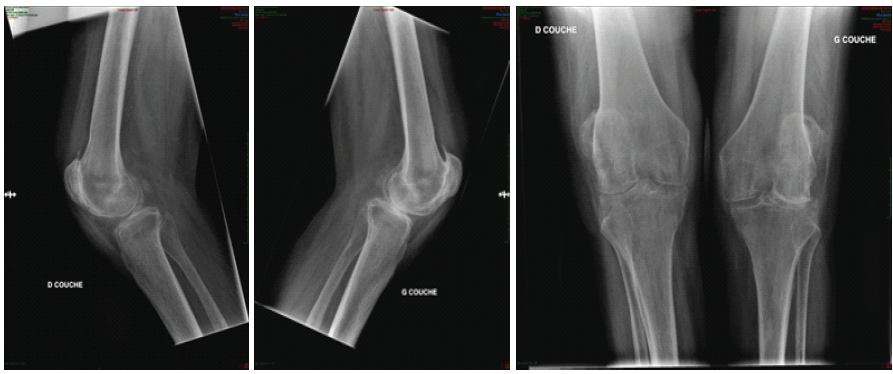

A 64-year-old female with a long-standing history of RA presented with bilateral knee ankylosis fixed in 40° of flexion, irreducible and painful. Functional disability was severe, rendering standing and walking impossible and leading to continuous bed confinement (Fig. 1).

Figure 1: Pre-operative X-ray.